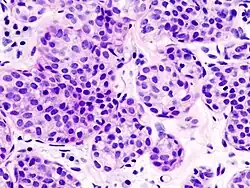

| Pleomorphic | Classical-appearing but with pleomorphic cells. It may include signet-ring cells, or plasmacytoid cells (pictured) which have abundant cytoplasm and eccentric nuclei. | ![]() |

Histopathology of invasive lobular carcinoma (ILC), next to lobular carcinoma in situ (LCIS)